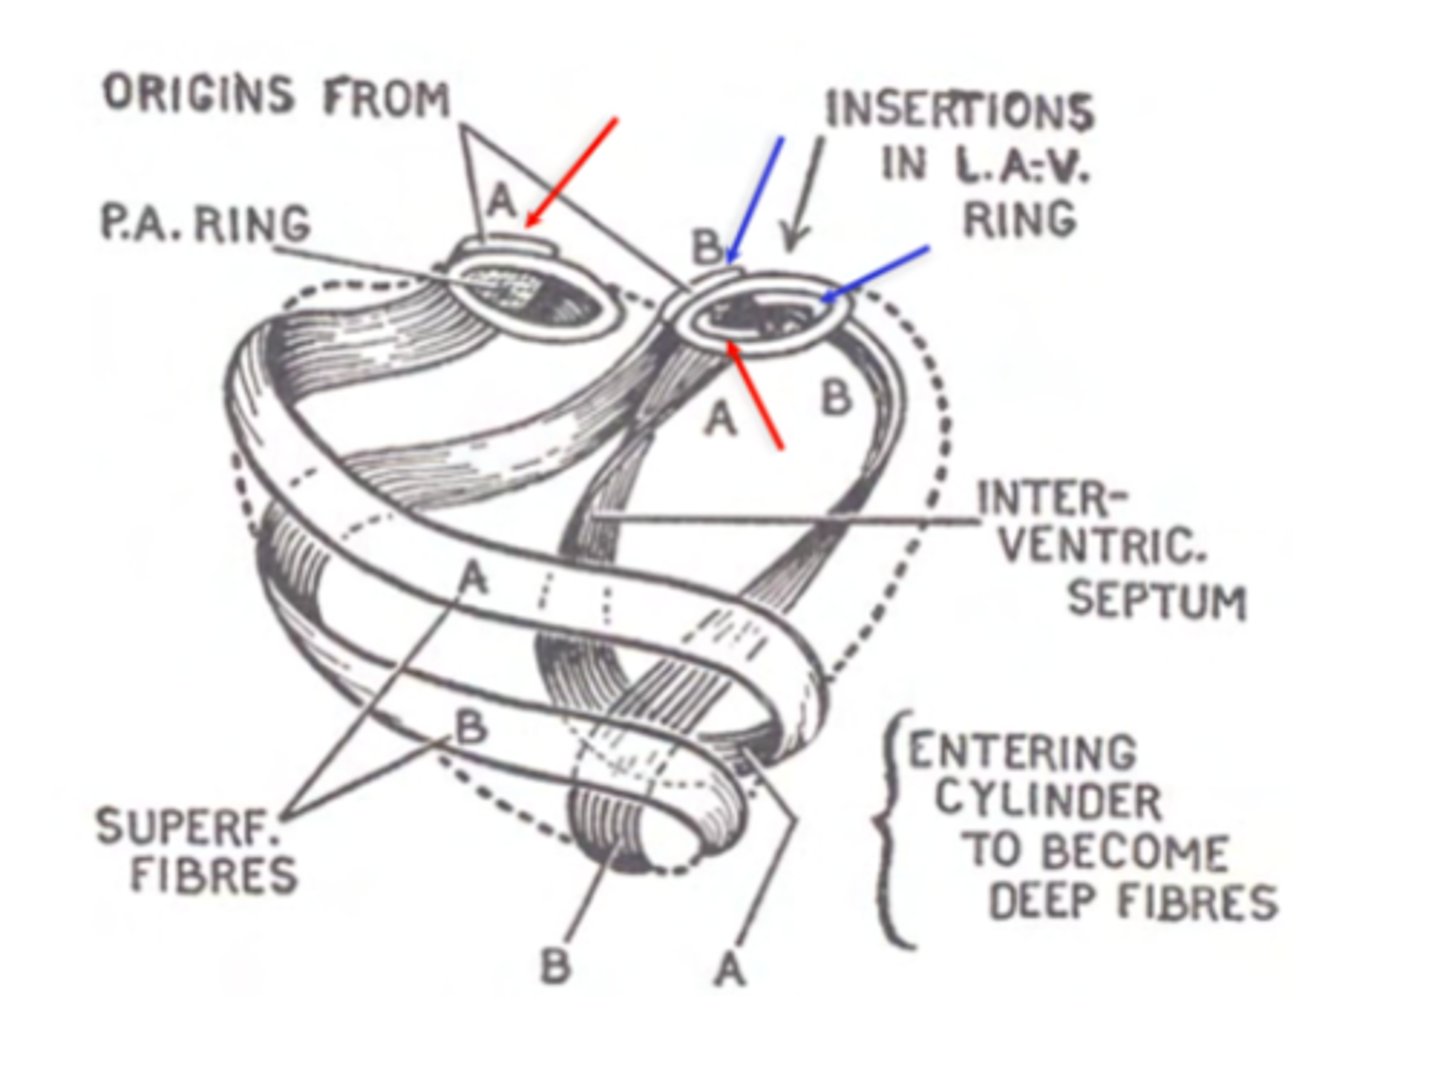

What are type A fibers in myocardium?

Start at one ring of the cardiac skeleton and finish at the other.

Form the interventricular septum

What are type B fibers in myocardium?

Begin at one ring and finish at the same ring where they started (either right or left).

Reinforce the ventricles

What are the layers of myocardium that divide the chambers of the heart?

left : superficial, middle and deep

right : superficial and deep

REMEMBER LEFT IS THICKER DUE TO THE HIGH PRESSURE OF THE AORTA